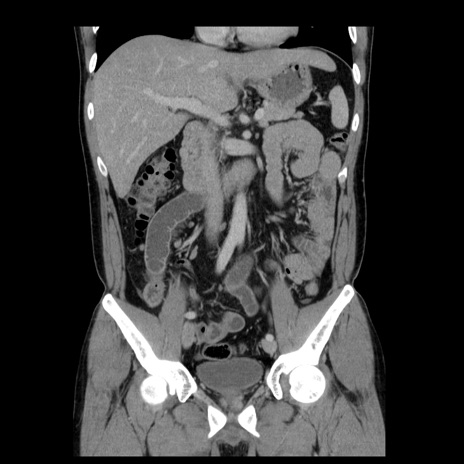

症例4(冠状断像)

【症例】30歳代男性

【主訴】腹痛、嘔吐

【現病歴】昨晩から突然の腹痛あり、その後嘔吐、軟便も出現。腹痛が改善しないため救急搬送となる。2日前にしめ鯖の食事歴あり。

【身体所見】意識清明、苦悶様、BP 135/90mmHg、BT 35.7℃、腹部:平坦、やや硬、心窩部〜臍部に自発痛、圧痛あり、筋性防御+、反跳痛-

【データ】WBC 8100、CRP 0.57